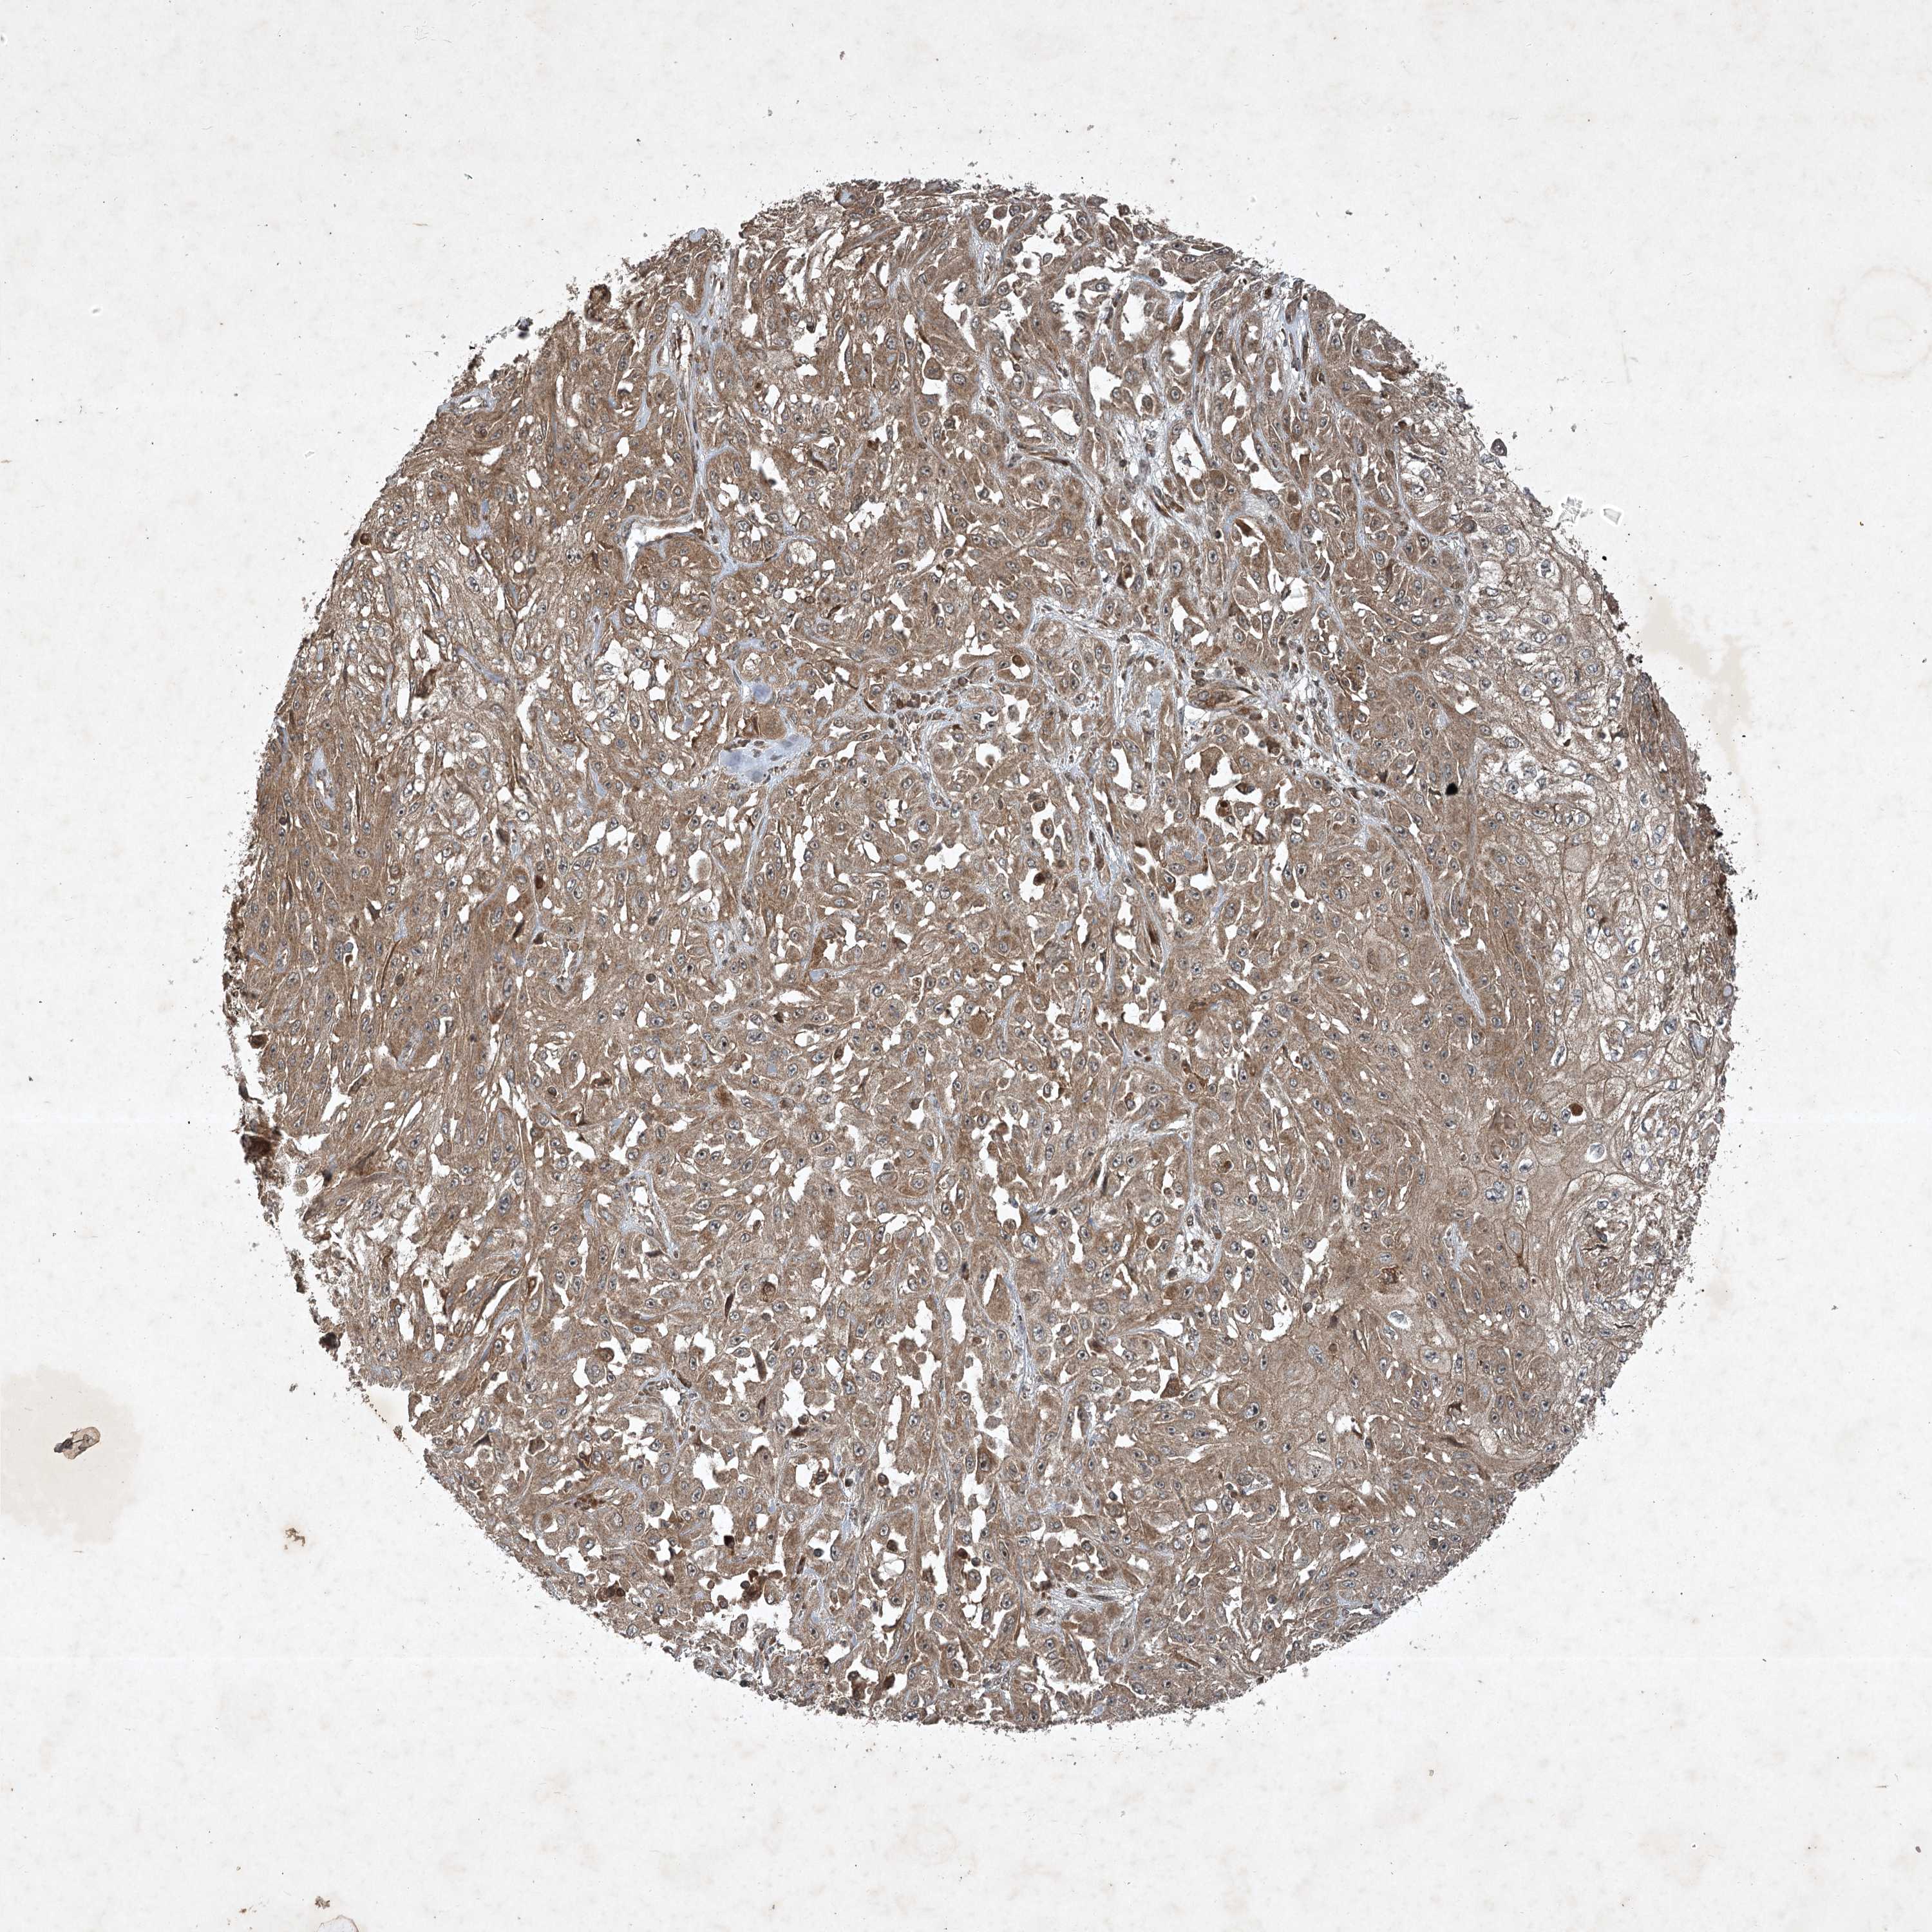

SKIN CANCER - Protein expressioni

A mouse-over function shows sample information and annotation data. Click on an image to view it in a full screen mode. Samples can be filtered based on level of antibody staining by selecting one or several of the following categories: high, medium, low and not detected. The assay and annotation is described here.

Antibody stainingi

Antibody staining in the annotated cell types in the current human tissue is reported as not detected, low, medium, or high, based on conventional immunohistochemistry profiling in selected tissues. This score is based on the combination of the staining intensity and fraction of stained cells.

Each image is clickable and will lead to virtual microscopy that enables deeper exploration of all samples and also displays staining intensity scores, fraction scores and subcellular localization as well as patient and tissue information for each sample.

Antibody HPA035729

Staining

High

Intensity

Strong

Quantity

>75%

Location

Nuclear

Basal cell carcinoma

Squamous cell carcinoma, NOS

Squamous cell carcinoma, metastatic, NOS